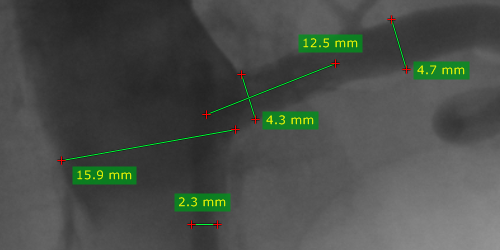

从 测量 下拉菜单中选择 长度(或按 L 键)。

将光标移到起点处,按住鼠标左键拖动画出线段,松开鼠标完成测量。

测量结果以毫米或像素显示(当图像文件中不包含校准数据时以像素显示)。

按住鼠标左键拖动线段本身或其端点,可移动整段线或调整端点位置。标注文字也可拖动到更合适的位置。